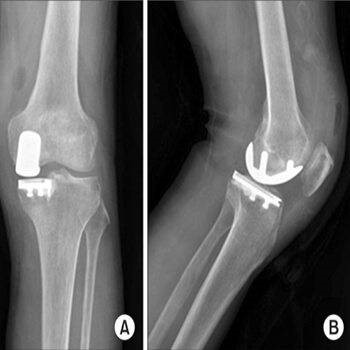

La prótesis total de rodilla es la cirugía más frecuentemente realizada para tratar la artrosis de rodilla. En una intervención con una historia de casi 50 años y es de las cirugías más exitosas que existen afortunadamente. Se realiza la sustitución del hueso desgastado mediante fijación de dos o tres implantes artificiales entre el fémur, la tibia y el fémur. Tras una minuciosa discusión con el paciente, el cirujano decidirá el tipo del implante a usar dependiendo de su edad, forma de los huesos (anatomía), nivel de actividad y calidad de hueso entre otros factores. Un minucioso estudio de planificación clínico antes de la cirugía permitirá la elección de los implantes que se requiere para adaptarlos y corregir la deformidad de la rodilla y de la pierna. Esa planificación hecha más habitualmente con radiografías permite elegir los implantes adecuados y prever los escenarios que pueden encontrarse en el quirófano – un paso imprescindible para el éxito de la cirugía. Los cirujanos de rodilla deben dominar un amplio repertorio de implantes para adecuarlo a cada situación. Los tres tipos de prótesis de rodilla son: la total, la unicompartimental y la femoropatelar.

La Protesis Total de Rodilla.

El que se usa de manera normal con excelentes resultados a largo plazo es la prótesis total de rodilla. Las prótesis de rodilla cementada consisten de tres implantes fijados al hueso con cemento: una arriba en el fémur (muy liso y hecho frecuentemente de Cobalto Cromo), una base implantada dentro de la parte proximal de la tibia tras resecar su superficie (de titanio) y un botón de plástico en la patela. Entre el fémur y la tibia se inserta un plástico de polietileno con propiedades especiales que limita el desgaste o rotura.